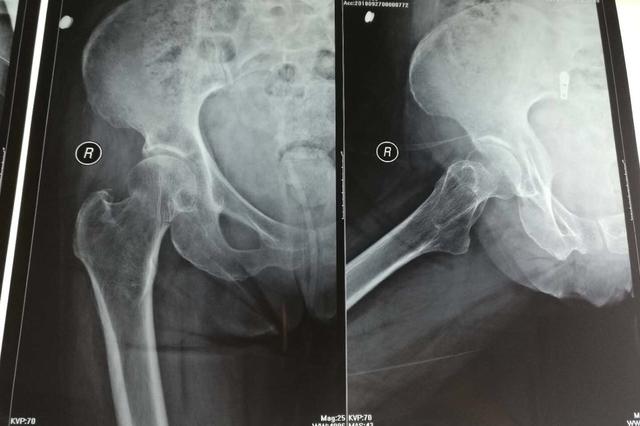

扬子晚报网9月28日讯(实习采访人员 艾陆琦)9月27日晚,新浪微博一网友发文称自己近八十岁的奶奶走在山西临汾建设路上,被在某餐饮店刚吃完饭出来的着西装男子撞倒,进医院检查后发现右侧股骨颈骨折需要手术,而撞人男子及其同伴不知去向,该网友在文后附上监控视频,希望有知情者能帮助寻找肇事者。经过网友的帮助,现视频中的两名男子已经找到并口头道歉,剩下一人至今不肯露面。

今天,扬子晚报采访人员联系上了老人的家属朱先生,提及老人现在的情况,朱先生表示很担心,因为医生诊断其股骨颈骨折,明天一早老人就要动手术,但毕竟已经是将近八十岁的人了,手术还是存在危险。朱先生告诉采访人员,老人被撞到后,家人已经联系了派出所调取监控,并且发布到网上,之后经过好心人的帮助,已经找到了视频里撞人的西装男子和黑衣男子,当天三人喝了酒,西装男子和黑衣男子也已经口头道歉,但书面和公开道歉暂时没有,并且丢下两元钱的男子还没出现,尽管前来道歉的两人联系过他,但他至今仍未露面。